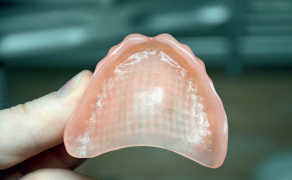

Materiały, o których będziemy mówić, noszą nazwę biomateriałów. Najprościej mówiąc, to substancje lub materiały, z których wytwarzane są określone struktury, urządzenia lub ich elementy mające bezpośredni kontakt z tkankami organizmu. Drugim ważnym aspektem jest to, że taki wyrób nie powinien oddziaływać w żaden sposób na organizm, z którym pozostaje w kontakcie. Takie funkcje spełniają materiały stomatologiczne umieszczane w jamie ustnej pacjenta. Z tego też powodu podlegają one odpowiednim regulacjom prawnym, a w większości krajów mogą być używane tylko te wyroby, które pozytywnie przeszły odpowiedni proces dopuszczenia do użytkowania.

Jednym z wymagań, które musi spełnić materiał, aby mógł być dopuszczony do sprzedaży, jest jego biozgodność (biokompatybilność). Pod tym terminem kryje się sposób, w jaki wpływa on na organizm ludzki, co oznacza, że musi być dobrze tolerowalny. Wśród nowoczesnych materiałów stomatologicznych można spotkać bowiem grupę [...]